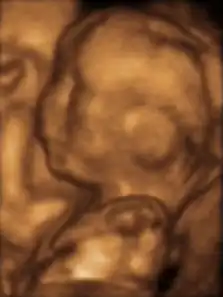

3D ultrasound

3D ultrasound is a medical ultrasound technique, often used in fetal, cardiac, trans-rectal and intra-vascular applications. 3D ultrasound refers specifically to the volume rendering of ultrasound data. When involving a series of 3D volumes collected over time, it can also be referred to as 4D ultrasound (three spatial dimensions plus one time dimension) or real-time 3D ultrasound.[1]

Obstetrics

3D ultrasound is useful, among other things, for facilitating the characterization of some congenital defects, such as skeletal anomalies and heart issues. With real-time 3D ultrasound, the fetal heart rate can be examined in real-time.[4][5]